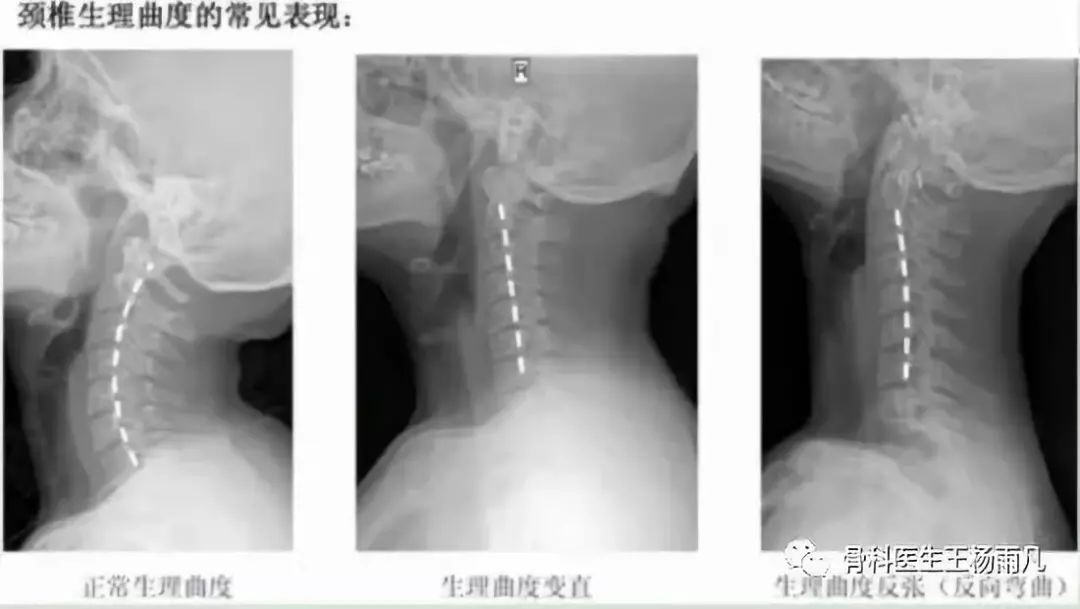

很多患者因为脖子疼,到医院拍了一个X片,报告上说,颈椎生理曲度变直,或者说颈椎反张,这些都说明存在颈椎的退变,这种情况下往往也伴有颈部肌肉的劳损。